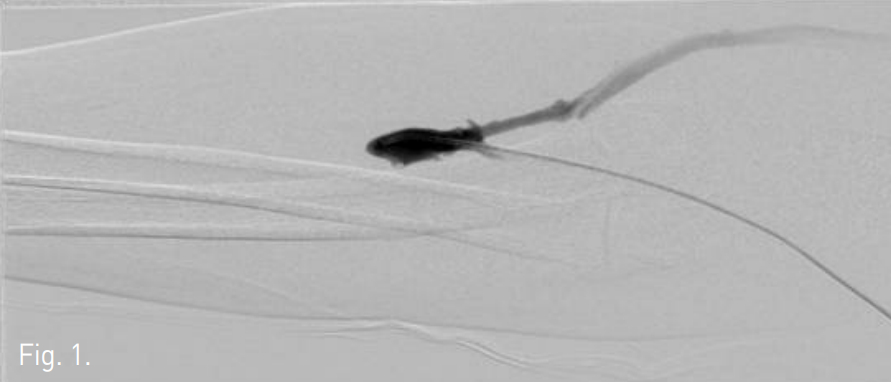

시술 당시 시행한 좌측 상지 fistulography에서 left distal cephalic vein의 total occlusion이 있다(Fig. 1). 초음파 검사에서 cephalic vein의 segmental occlusion이 fibrous cord 처럼 보인다.

Fig. 1

A fistulogram shows total occlusion of dis tal cephalic vein proximal to the anastomosis.